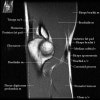

1. Coronal section

1) Collateral ligament

2) Common extensor/flexor tendon group patholgy as well as epicondylitis